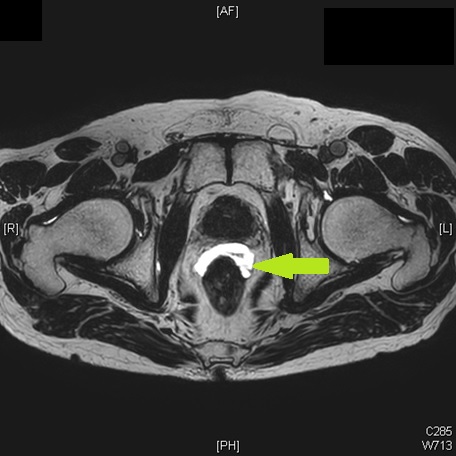

エコーを用いてシードを留置している様子

前立腺内の線量分布の確認

スペーサゲル